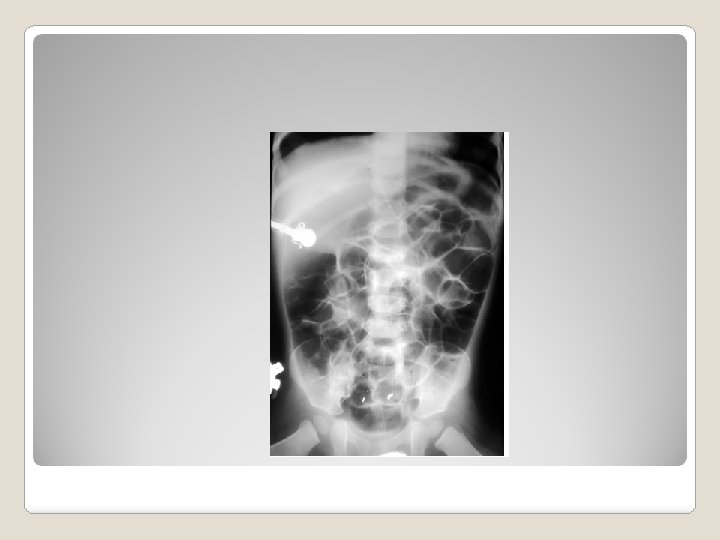

Diagnosis BLL > _______ mcg/dl X Rays Diagnosis BLL > _______ mcg/dl X Rays